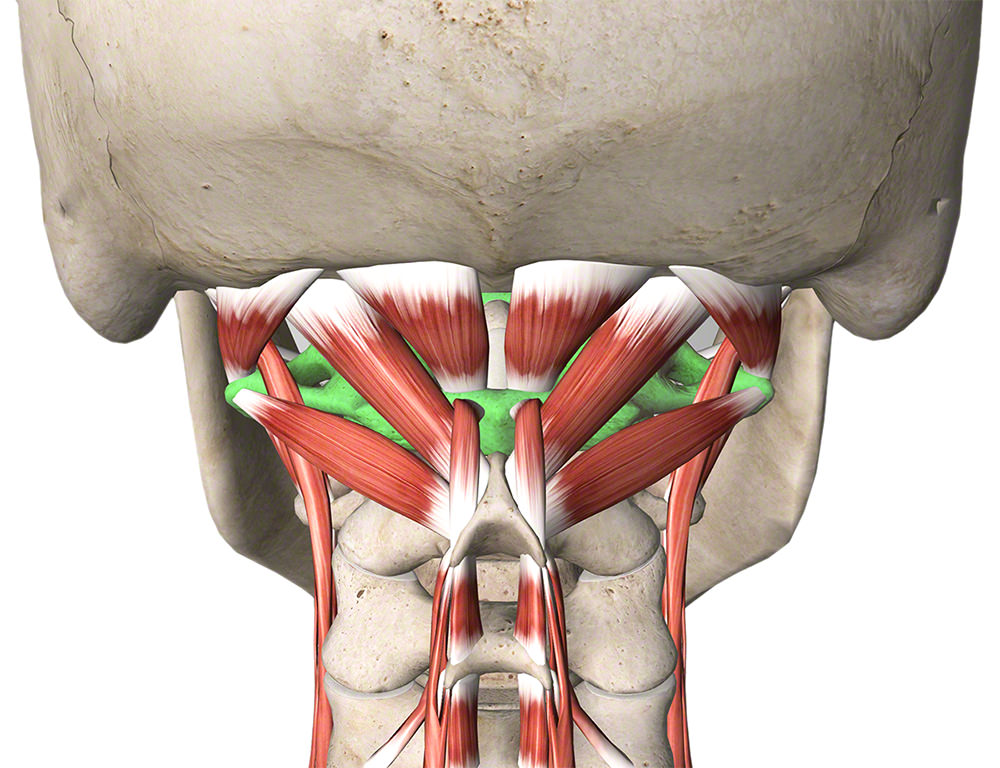

Queste quattro paia di piccoli muscoli, che collegano la parte bassa del cranio alla parte superiore delle cervicali, aiutano nella rotazione e nell’estensione della testa. Questi muscoli sono costantemente coinvolti nel mantenere la testa inclinata verso l’alto per guardare frontalmente.